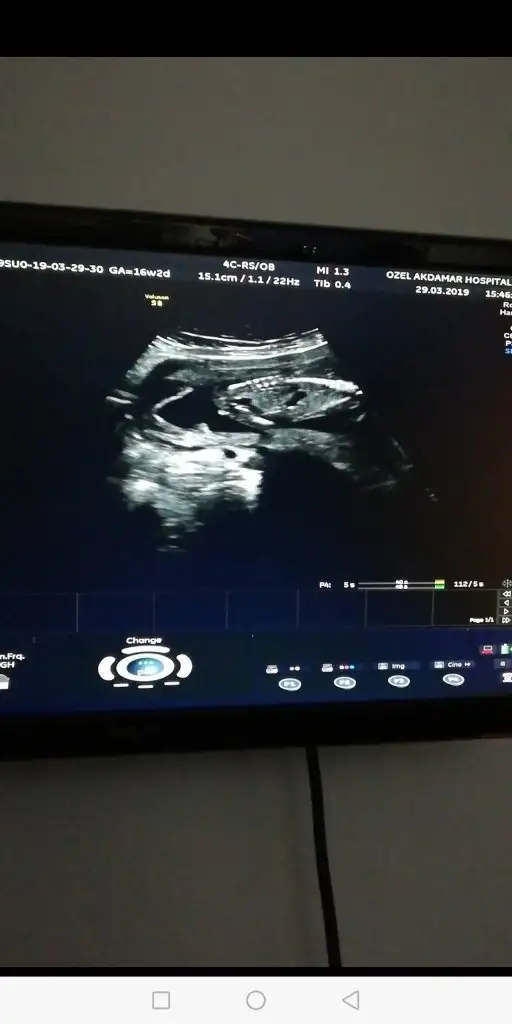

Senin usg de bebeğin duruş pozisyonundan dolayı emin olamadım canım.kesin demiyim ama son kararım kızBen hiç anlamıyorum ama yrn kontrolüm var eğer usg bakarsa daha net görünür sanırım yine resim koyarım![]()

Kız benceBana da yorum yaparmisnz

Insallah canm ya iki dktrda erkege benzetti ama kesin deil dedi alisveris yapma dedilerKız bence

Valla kesin konuşmayayım tabi.iyice emin olduklarıma kesin diyorum ama bu usg ye kesin diyemiyorum.ben bu usg de kıza benzettim.ama erkek te olabilir.nubu kıza,kafa yapısı erkeğe benziyor.hayırlısını versin rabbimInsallah canm ya iki dktrda erkege benzetti ama kesin deil dedi alisveris yapma dediler